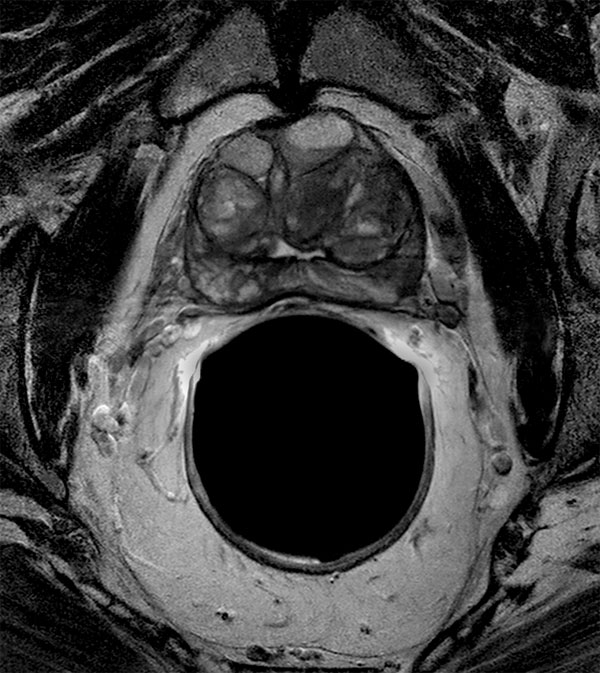

75-year old male. dS Endo coil used to visualize tumor in peripheral gland.

Axial T2w TSE